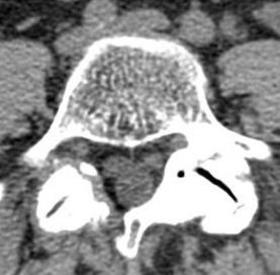

La stenosi lombare è un'abnorme ristrettezza del canale vertebrale osteolegamentoso e/o dei forami intervertebrali (fig.1), ed è causa di una compressione del sacco tecale e/o delle radici spinali caudali (fig.2). Il restringimento può essere mono o plurisegmentario. Le…